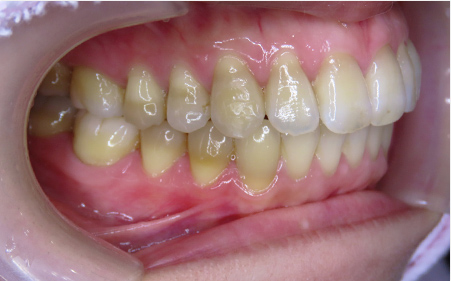

CASE08

Before

After

| 施術名 |

インビザラインコンプリヘンシブを用いた矯正治療(叢生) |

| 治療期間 |

1年 |

| 治療費 |

880,000円(税込) |

| リスク |

マウスピース装置により疼痛・咬合時痛を生じる事があります。割れたり壊れたりする事があります。 |

歯科医師からのコメント

「上顎八重歯が気になる」で来院されました。分析すると、軽度なねじれでしたのでインビザラインGoにて治療をすすめていきました。マウスピースを積極的に使用し、順調に治療がすすんでいきました。仕上がりにとても満足しておられました。